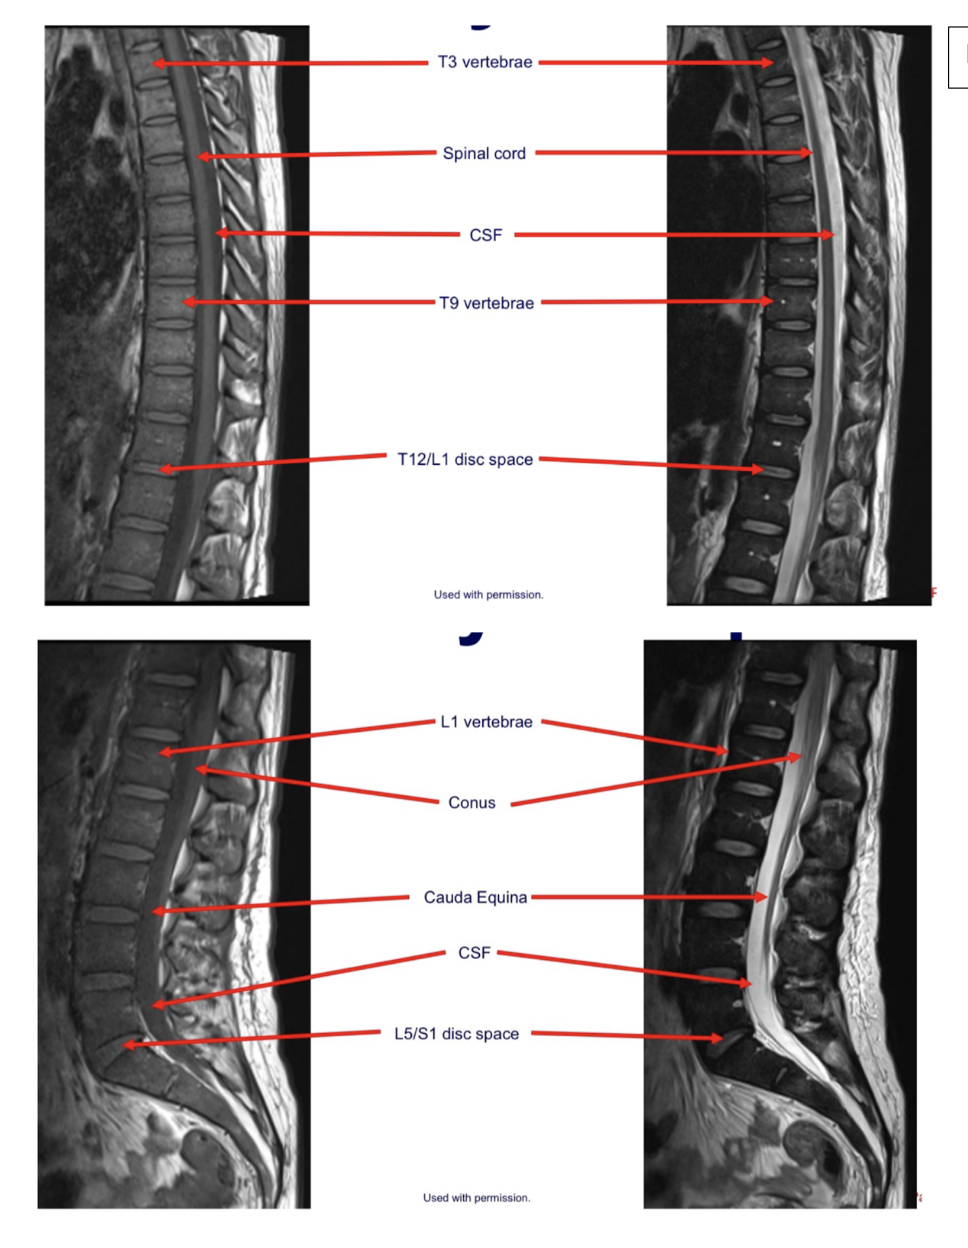

Sequence + Pathology?

T1,T2

• Cauda Equina syndrome

• L5/S1 disk space herniation compressing the cauda equina.

• Signal intensity is lost in T2 sag as you get to L5/S1 disk space.